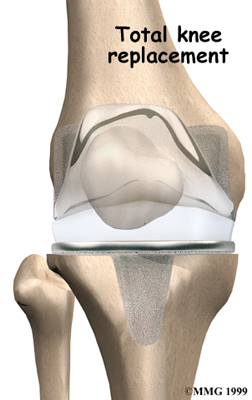

Artificial Knee Replacement

An artificial knee replacement is the ultimate solution for advanced knee OA.

Surgeons prefer not to put a new knee joint in patients younger than 60. This is because younger patients are generally more active and might put too much stress on the joint, causing it to loosen or even crack. A revision surgery to replace a damaged prosthesis is harder to do, has more possible complications, and is usually less successful than a first-time joint replacement surgery.

Related Document: FYZICAL South Meridian's Guide to Artificial Joint Replacement of the Knee